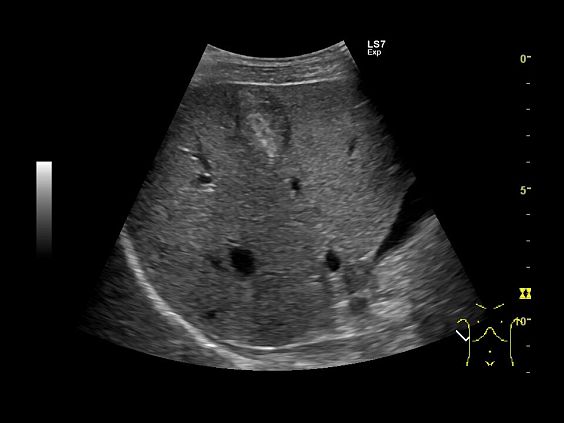

Клинические изображения

Logiq S7 XDclear — УЗИ аппарат нового поколения, который обеспечивает простой и комфортный рабочий процесс, высокую производительность и предлагает широкий набор современных инструментов для проведения уверенной диагностики. Его расширенный функционал включает такие возможности как B-Flow — недопплеровская технология отображения кровотока в B-режиме, компрессионная эластография (качественная и полуколичественная), количественный анализ васкуляризации, функцию В-Steer+ — изменение угла наклона УЗ луча в B-режиме, 3D/4D диагностику и мультимодальную визуализацию.

- Абдоминальные исследования

Ультразвуковой аппарат LOGIQ S7 XDclear предназначен для использования специалистами из различных областей диагностики. Его расширенный функционал включает такие возможности как B-Flow — недопплеровская технология отображения кровотока в B-режиме, компрессионная эластография (качественная и полуколичественная), количественный анализ васкуляризации, функцию В-Steer+ — изменение угла наклона УЗ луча в B-режиме, 3D/4D диагностику и мультимодальную визуализацию.